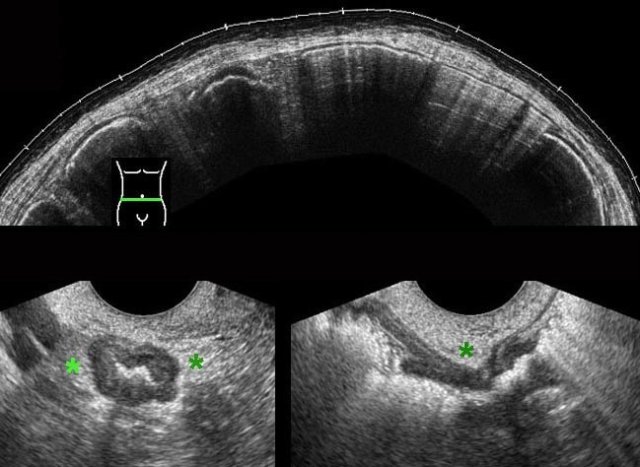

DIE implants on the outer surface of the colon in four different patients.

DIE implants (*) in Douglas pouch, are asymmetrically localized, solid, hypoechoic, poorly vascularized masses, which are continuous with the outer hypoechoic muscularis layer of the colon.

The overlying hyperechoic submucosa,  and also the colonic mucosa are generally intact. This explains also why blood in the stool is quite rare in DIE.

The outer contour of these hypoechoic masses is mostly firmly adherent to uterus and/or cervix. Often there is spiculation or “tethering” visible on the outer margins.

Adherence to the uterus and cervix can be demonstrated by gently pushing with the probe to-and-fro.

Whereas the normal sigmoid and rectum can easily be pushed away from the uterus with the probe (“sliding phenomenon”), the adhesions (arrow) belonging to DIE (*) block the entrance of the probe into the posterior fornix.

In this videoclip, the transvaginal probe is gently moved to-and-fro.

The implant (*) has developed firm adhesions between uterus and colon, which prevent entering of the probe deeper in the direction of the sacrum.

In the normal situation, uterus and colon can be easily be pushed aside.